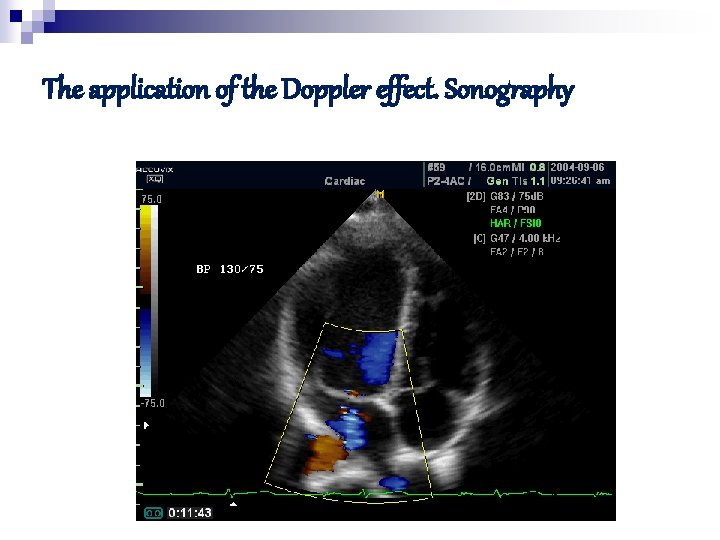

The application of the Doppler effect. Sonography Liver Kidney

The application of the Doppler effect. Sonography